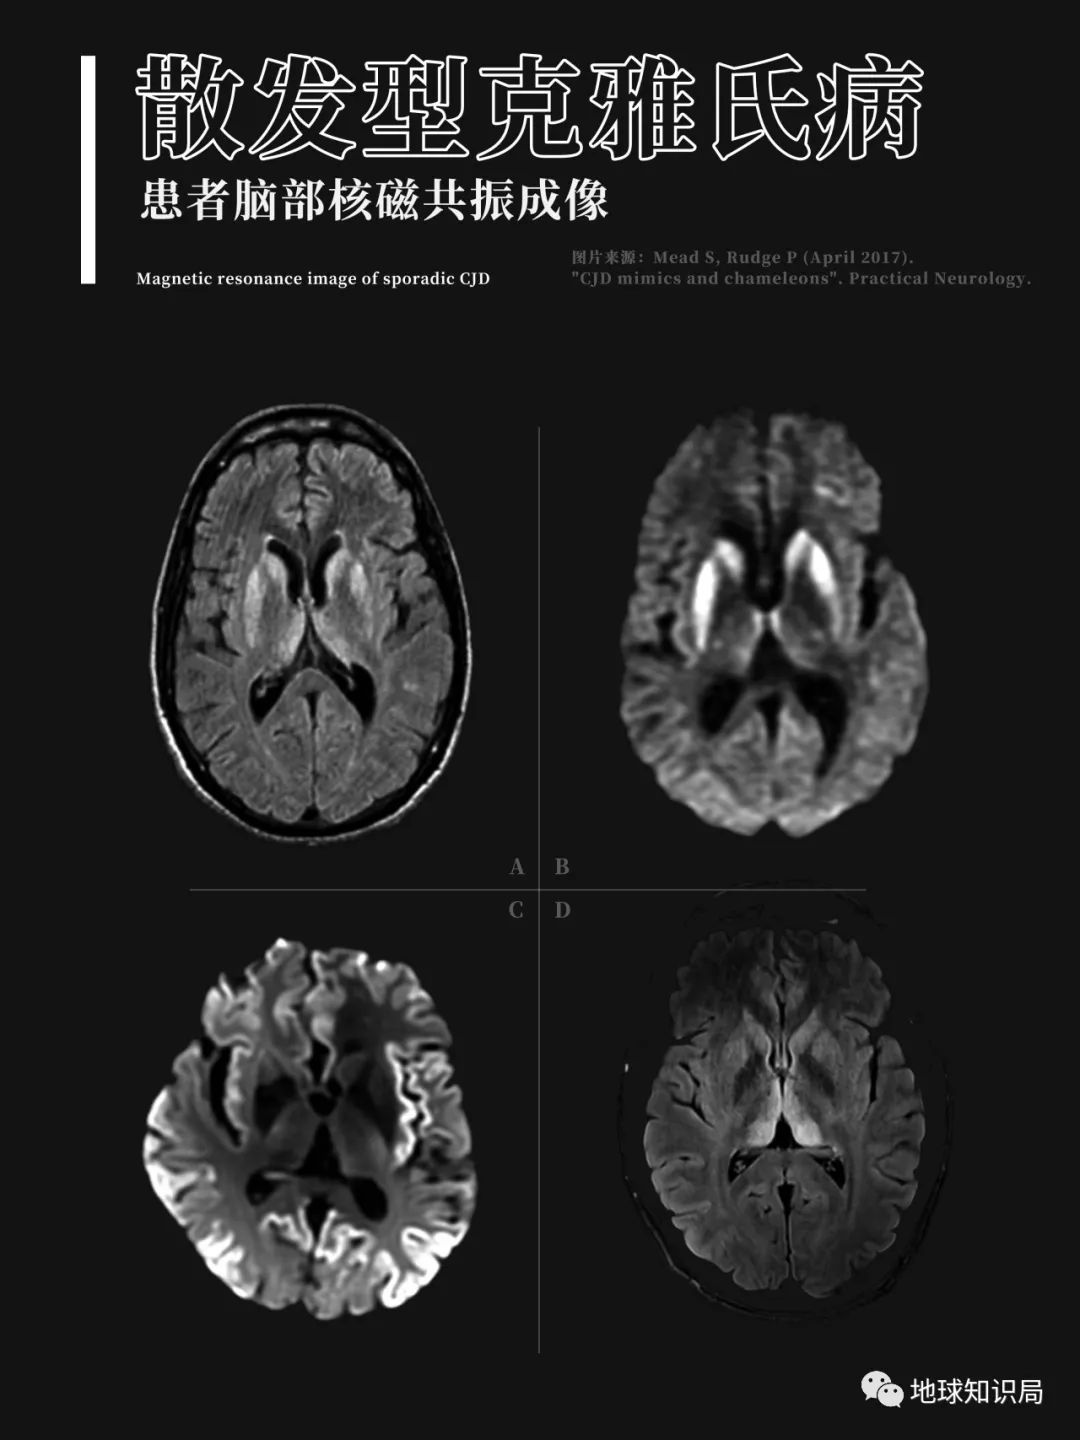

大約同一時期,研究者就發現了庫魯病和羊瘙癢症的一些相似之處:包括類似的症狀、難以被殺滅的病原體等。此外,研究者們還想到了早年間的另一種疾病——克雅氏病。

這種早在20世紀初就被明確記錄的疾病通常有如下表現:起病緩慢,開始時出現記憶力減退及頭痛,之後迅速判斷力下降、人格障礙,定向力障礙,最終患者完全痴呆,並有共濟失調和四肢肌肉的震顫抽搐。

無論是羊瘙癢症,還是庫魯病、克雅氏病,解剖提示這些患病個體大腦出現了大量異常的空洞,所有這一切都説明這些疾病是由同一種病原體造成;同時還表明,存在一種未知的病原體,它不是細菌,也不是病毒,甚至可能顛覆以往對生命的定義。

大腦萎縮,空洞明顯▼